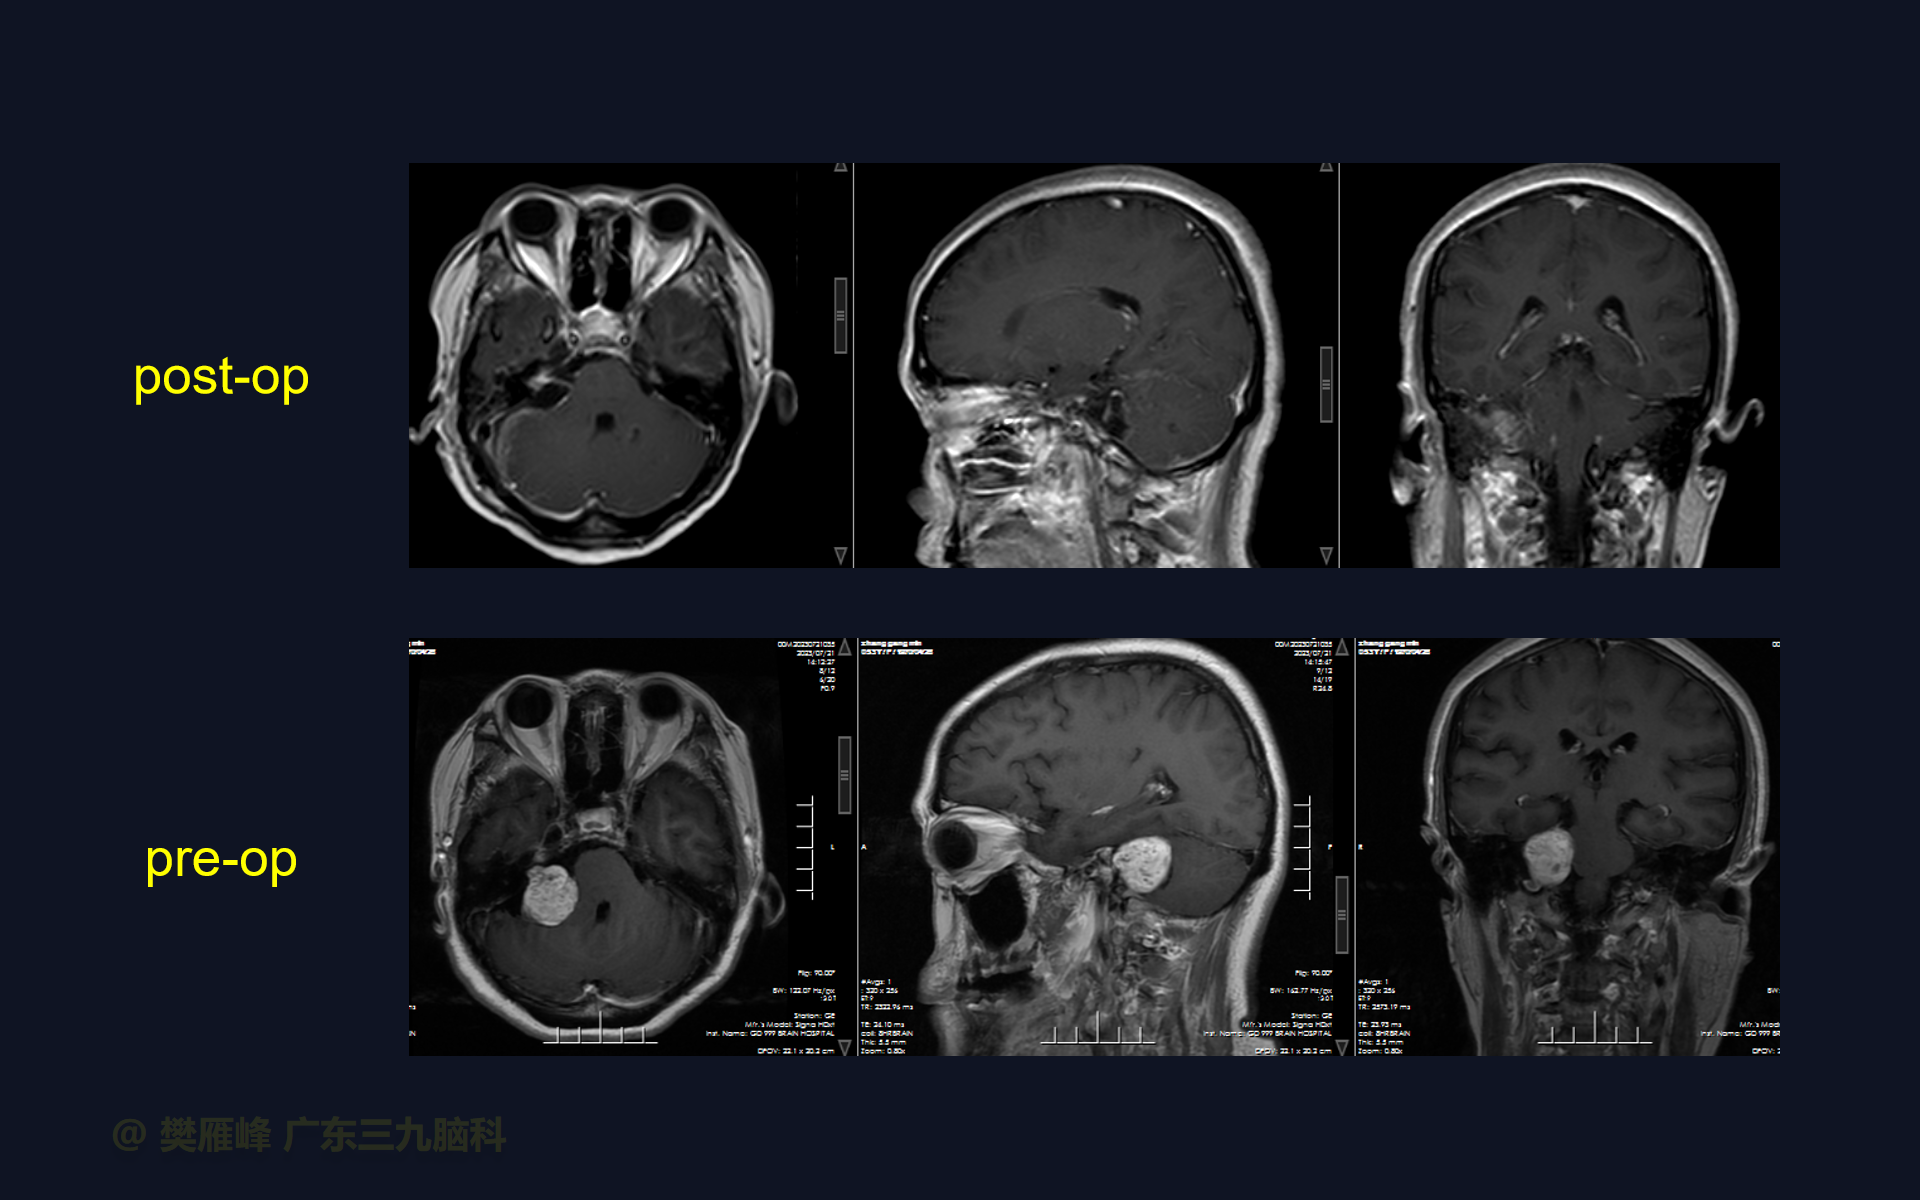

在这个二维手术视频中,展示了一种经枕下乙状窦后入路肿瘤包膜下分离并保留面神经。患者是一名53岁的男性,有1月的左耳听力下降、无步态不平衡病史,神经影像学显示右侧桥小脑角区T1低信号,T2不均匀高信号,DWI序列呈等、低信号,增强不均匀强化的听神经瘤。他接受了经乙状窦后入路保留面神经的方法,以实现肿瘤全切除。术后轻微面瘫,听力同术前改变,神经影像学显示肿瘤全部切除。我们展示了包膜下切除肿瘤和保护面神经的细微差别和技术要点。

在这段手术视频中,展示了一名53岁男性的病例,他因右耳听力下降1月余发现的右侧听神经瘤